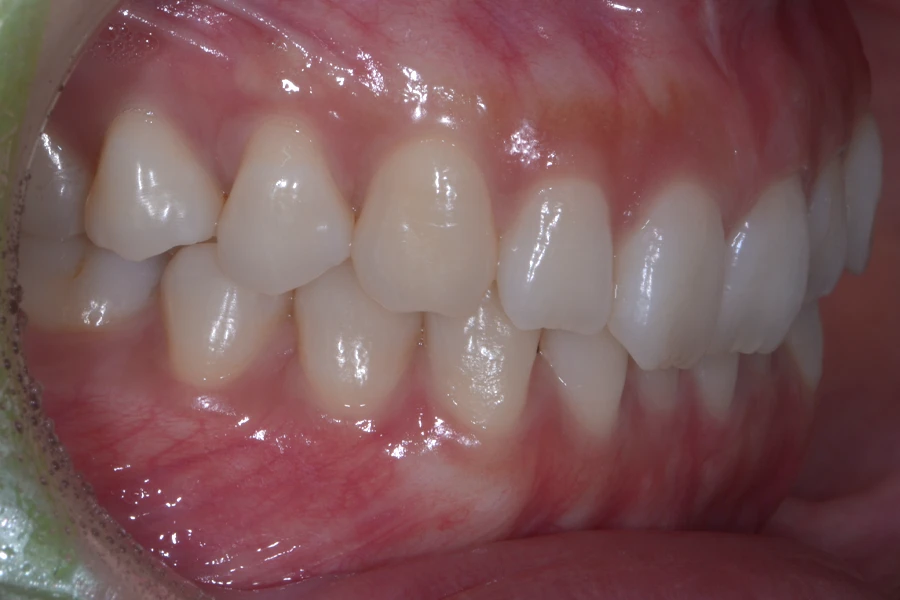

【20代女性】

結婚式までに前歯を綺麗に整えたい

治療前

主訴 結婚式までに前歯を綺麗に整えたい

期間 10か月

費用 40万円(別途調整料)

治療内容 上下顎ラビアル矯正(表側矯正)

治療に伴うリスク 後戻り